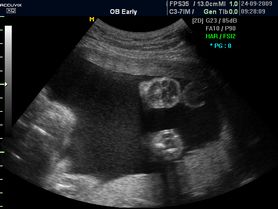

Płód w 9 tygodniu ciąży (bliźniaki jednokosmówkowe) -zdjęcia